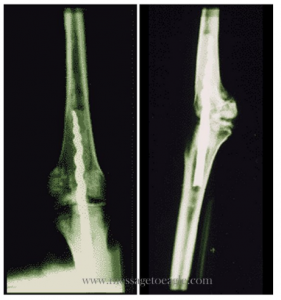

En 1996, la découverte, lors d’une fouille, du premier exemple connu de rattachement ancien d’un membre fait sensation. Il s’agit de la momie vieille de 2600 ans du prêtre Usermontua. En regardant l’imagerie radiographique, on remarque une vis métallique entre la cuisse et le bas du genou. Et selon le Dr Richard Jackson, chirurgien orthopédiste pour l’équipe sportive de Brigham Young University dans l’Utah aux États-Unis, la broche était faite de matériaux biomécaniques «que nous utilisons encore pour nous assurer d’obtenir une bonne fixation dans l’os stabilisateur!»